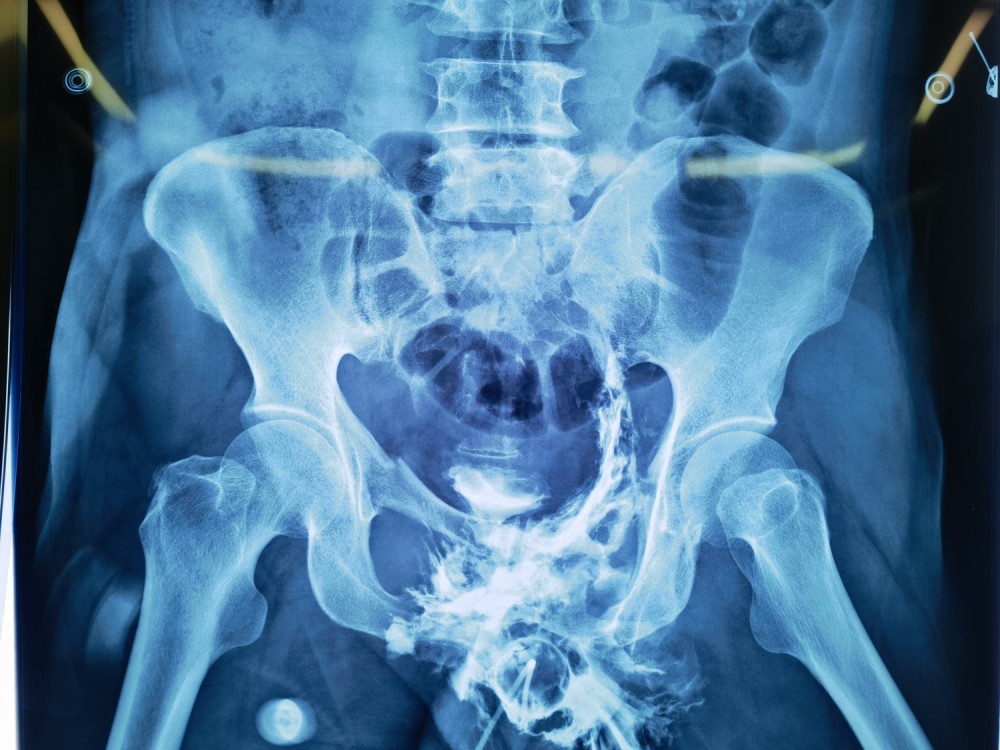

为能更快使患者得到救治,于成涌副主任医师紧急向所在医疗组成员创伤外科中心贾燕飞主任医师、创伤外科中心A区副主任张立峰及关健医师进行病例汇报及病情讨论,并将情况向医务部汇报、备案,依据损伤控制理论决定为该患者进行急诊手术,及时固定骨盆环,避免骨折移位造成二次损伤。在为患者紧急进行术前准备的同时,普通外科吕冰副主任医师团队也制定了剖腹探查的抢救方案,麻醉科手术中心紧张有序地为抢救手术做好准备,协调输血科为抢救患者充足准备血液制品,并请重症医学科副主任包道日娜会诊,为术后接收患者做好充足准备。全院多个科室通力合作,争分夺秒的抢救患者,每多做一份努力,就多一分抢救成功的机会。

麻醉手术中心乌兰娜日医师为患者行全身麻醉后,普通外科吕冰副主任医师团队及创伤外科中心A区关健医师组成的手术团队迅速行剖腹探查术。术中可见,患者膀胱多处裂伤(最长可达5cm),尿道断裂、毁损严重,且盆腔内多处大量出血。手术团队快速修补膀胱并进行造漏,术中拟探查活动性出血时发现出血部位于盆腔深处,难以探及。立即请综合外科李鹏飞医师会诊,李鹏飞医师考虑为髂内动脉分支出血,为快速止血挽救患者生命需行高选择性髂内动脉分支栓塞术,遂同唐克成医师急行手术治疗。随后,我科医师成功实施骨盆骨折闭合复位外固定治疗,患者术中出血约1700ml,输同型红细胞8U、血浆790ml。术后,患者生命体征平稳,转入重症医学科继续治疗。

骨盆骨折外固定架固定术后X片